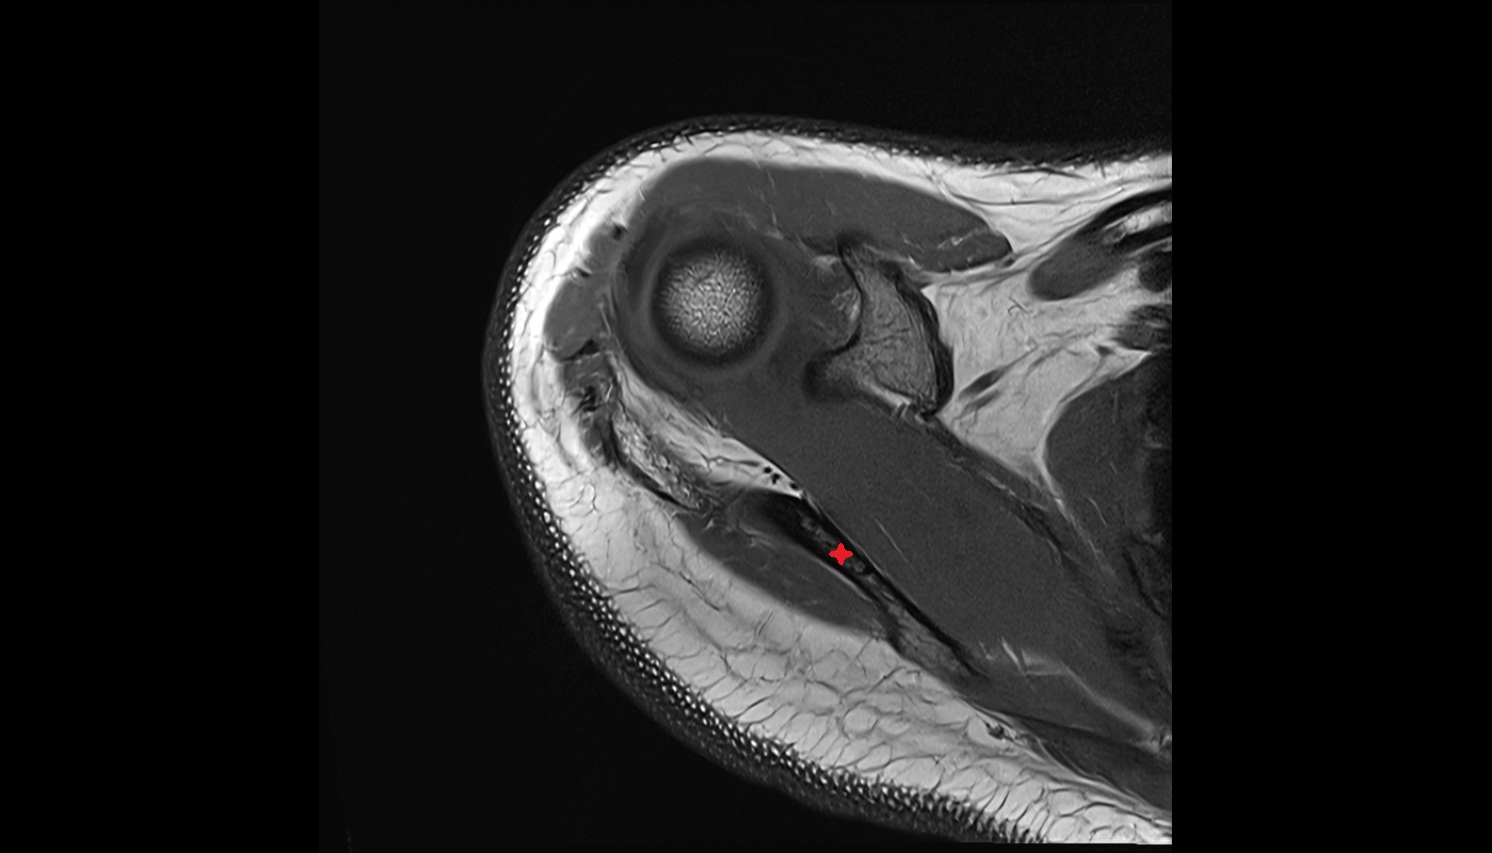

- Glenoid labrum

- Shoulder joint (glenohumeral joint)

- Articular cartilage of glenoid fossa

- Glenohumeral ligaments

- Superior glenohumeral ligament

- Middle glenohumeral ligament

- Inferior glenohumeral ligament

- Glenohumeral joint capsule